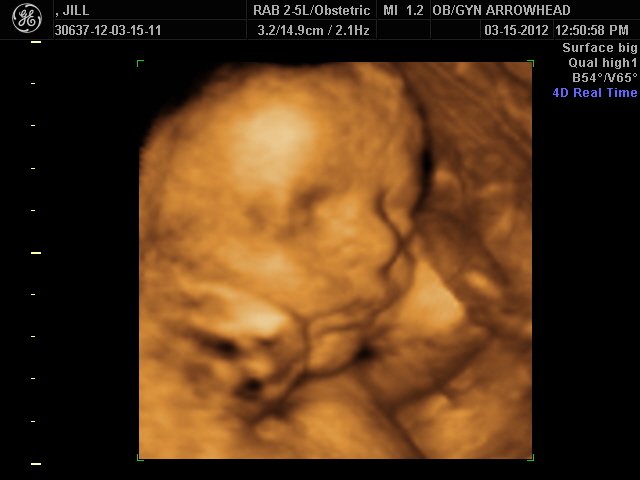

We offer complimentary 3D/4D Ultrasounds to all our OB patients around 30 weeks! The following photos are some examples of our work, shown with permission from our patients.